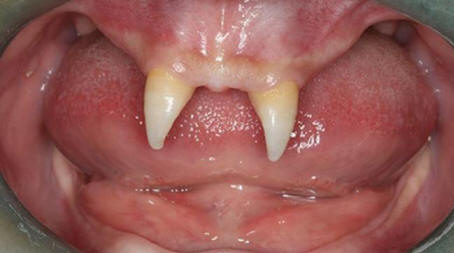

A kínai fiú két nagyon éles első fogat nőtt fel így vámpírnek tűnik. 2012 decemberében A Wang Hui nevű anya fiát, Wang Penfeit vitte a helyi emberhez kórház vizsgálatra. Chongqing Municipal Boy után a születés nagyon rosszul növekszik, és a szájában két élesnek látszott norvég menyhal.

Wang Hui megpróbálta megtudni ezeknek a fia megjelenésének okát rendellenes képződmények, és számtalan látogatott orvosok, de ez nem hozott sok sikert. Orvosok A Délnyugati Kórház szerint fia megtehető műtét csak akkor, ha felnőtté válik.

fénykép nyílt forrásokból

Ennek a műveletnek a költségei 70 000 és 80 000 között változhatnak RMB, körülbelül 15 000 dollár. Wang Hui szerint fia egyre inkább válik egyre inkább visszavonulnak, és gyakran harcolnak osztálytársakkal, akik suttognak róla, vagy figyelmesen néznek rá.